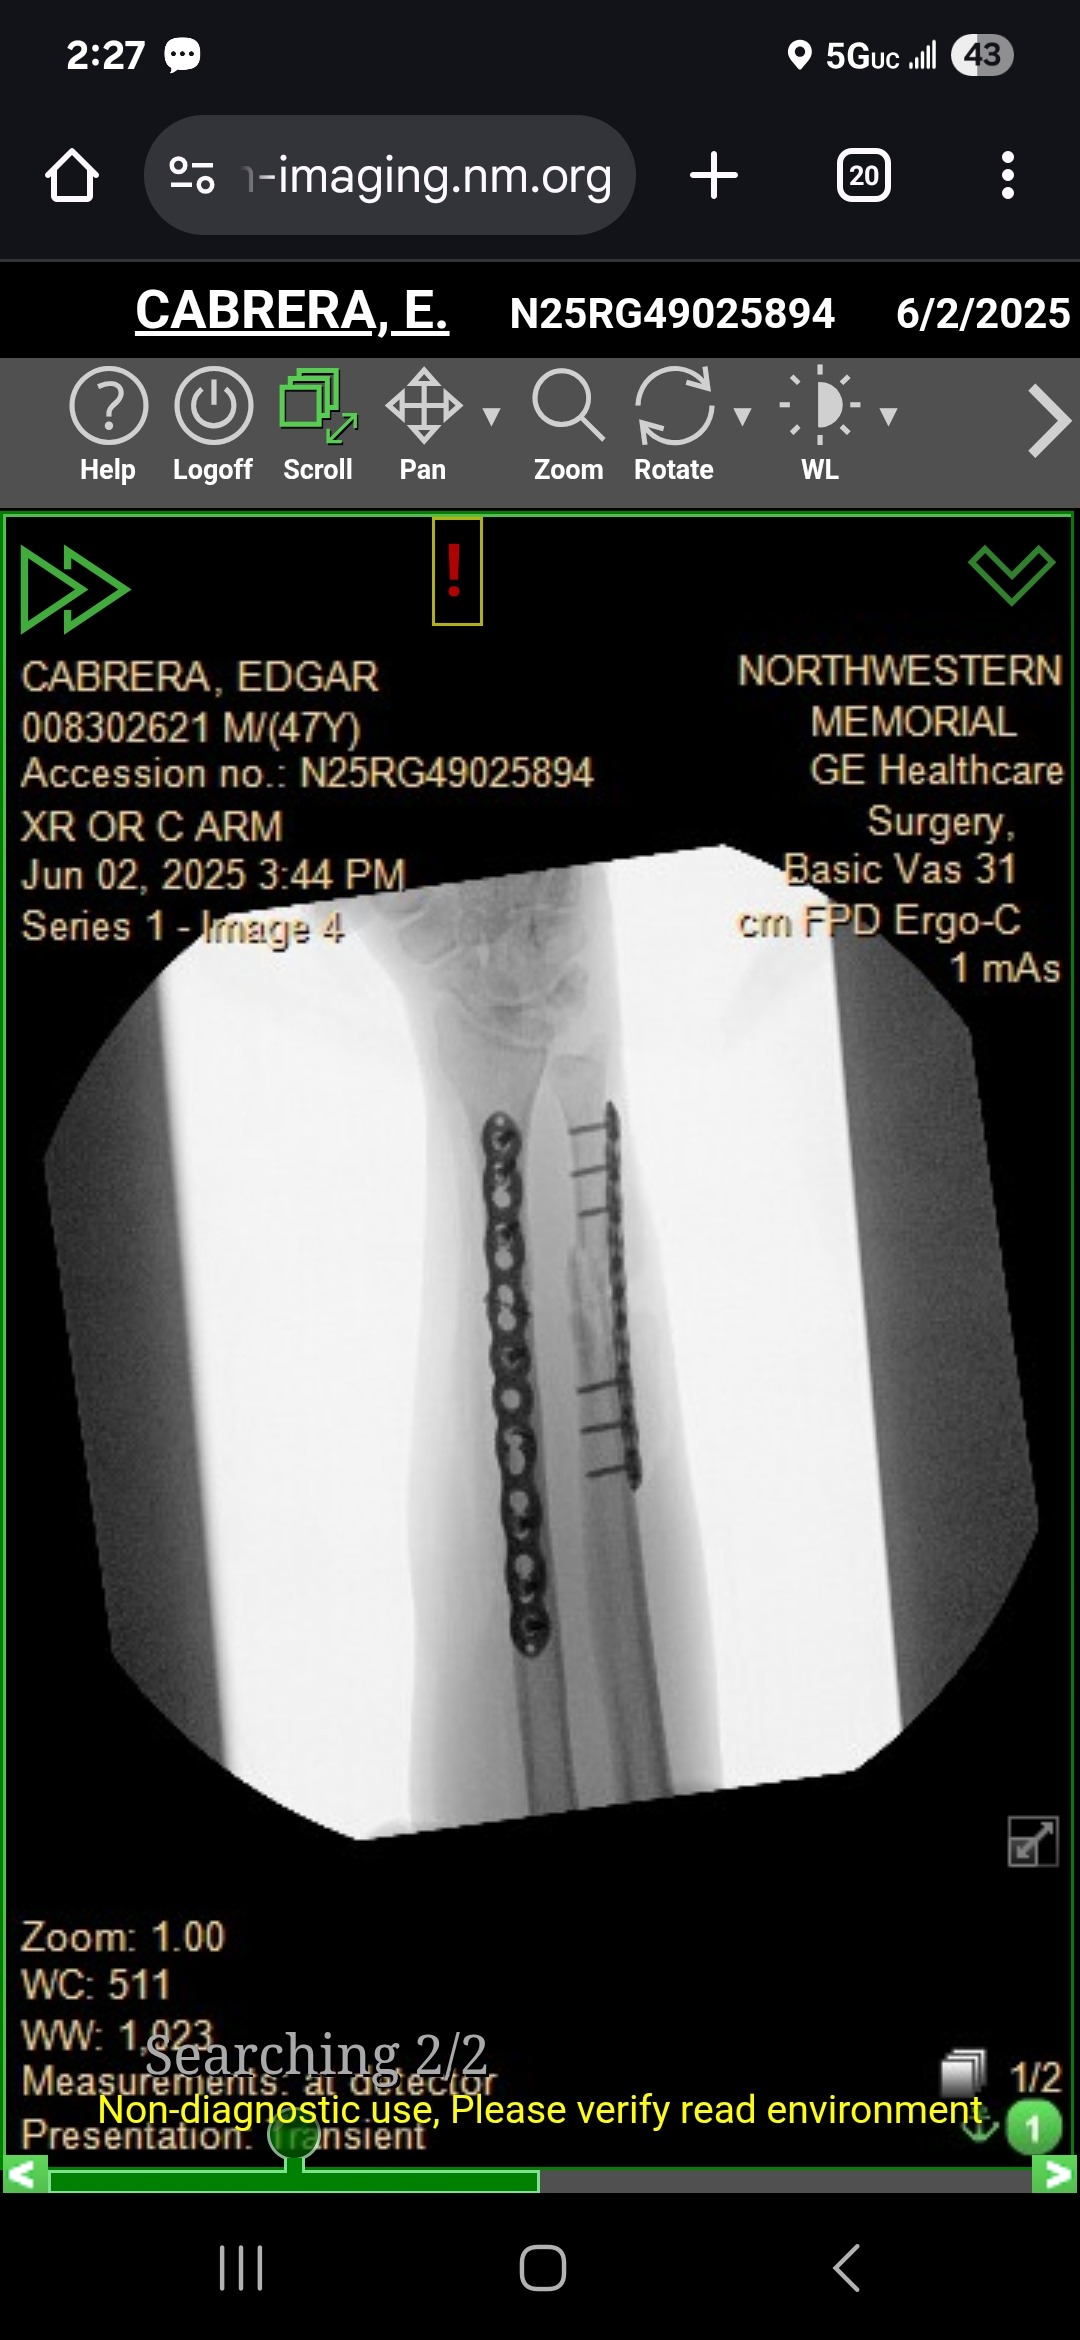

Hello everyone, my name is Ed Cabrera, and I was involved in a bike accident on June 1, 2025. I ended up with a broken arm that went clean through my skin and needed surgery, for which they put steel plates and screws in my arm.